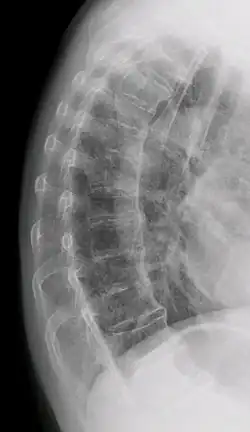

![]() | |

| DISH in an 80 year old female, also with T11 fracture. | |